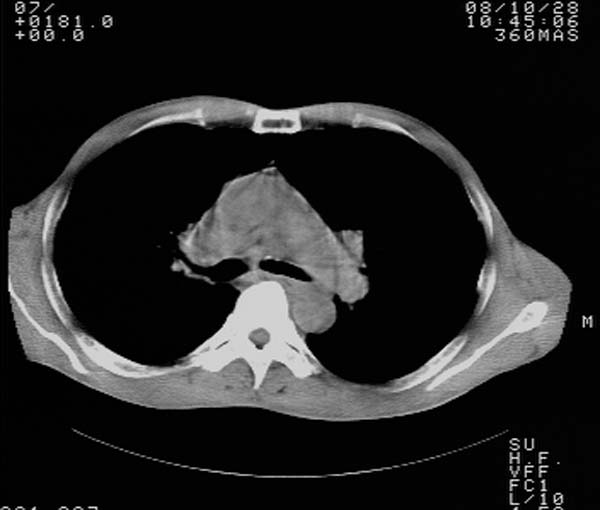

m,65y。半年前发现颈小结节,逐渐增多增大,现双侧耳后、颌下及颈部表浅淋巴肿大。胸片示双肺门增大。外院曾穿刺诊断为淋巴结核。在我科作胸腹部ct,我们觉得外院病检有误。现将图像上传请战友讨论。

纵隔内及腹膜后广泛淋巴结肿大,脾大,肝内似可见低密度影,结合病史半年前发现颈小结节,逐渐增多增大,现双侧耳后、颌下及颈部表浅淋巴肿大。考虑淋巴瘤。

我们也是首先考虑淋巴瘤。只是外院病检报告是结核。让人迷惑。肝左叶多发低密度占位,没增强不好定论。

纵隔,双肺门腹膜后多发淋巴结重大,非融合,肝脾轻度肿大,双肺野弥漫性小结节;考虑淋巴瘤,结节病可能性

现有资料不能明确!建议行强化及高分辨扫描。胸膜下可见小结节灶。分析思路:按可能性排序:结节病,淋巴瘤,结核。

纵隔内,双肺门、腋窝及腹膜后多发肿大淋巴结影,肺内小结节影,肝脾体积增大,支持淋巴瘤。肝内多发低密度影,考虑小囊肿。